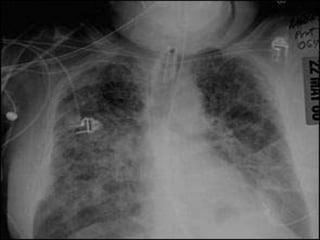

Diseased Lungs Do

Not Fully Collapse,

Despite Tension Pneumothorax

…and

They cannot always

be fully “opened”

Dimensions of a fully

Collapsed Normal Lung